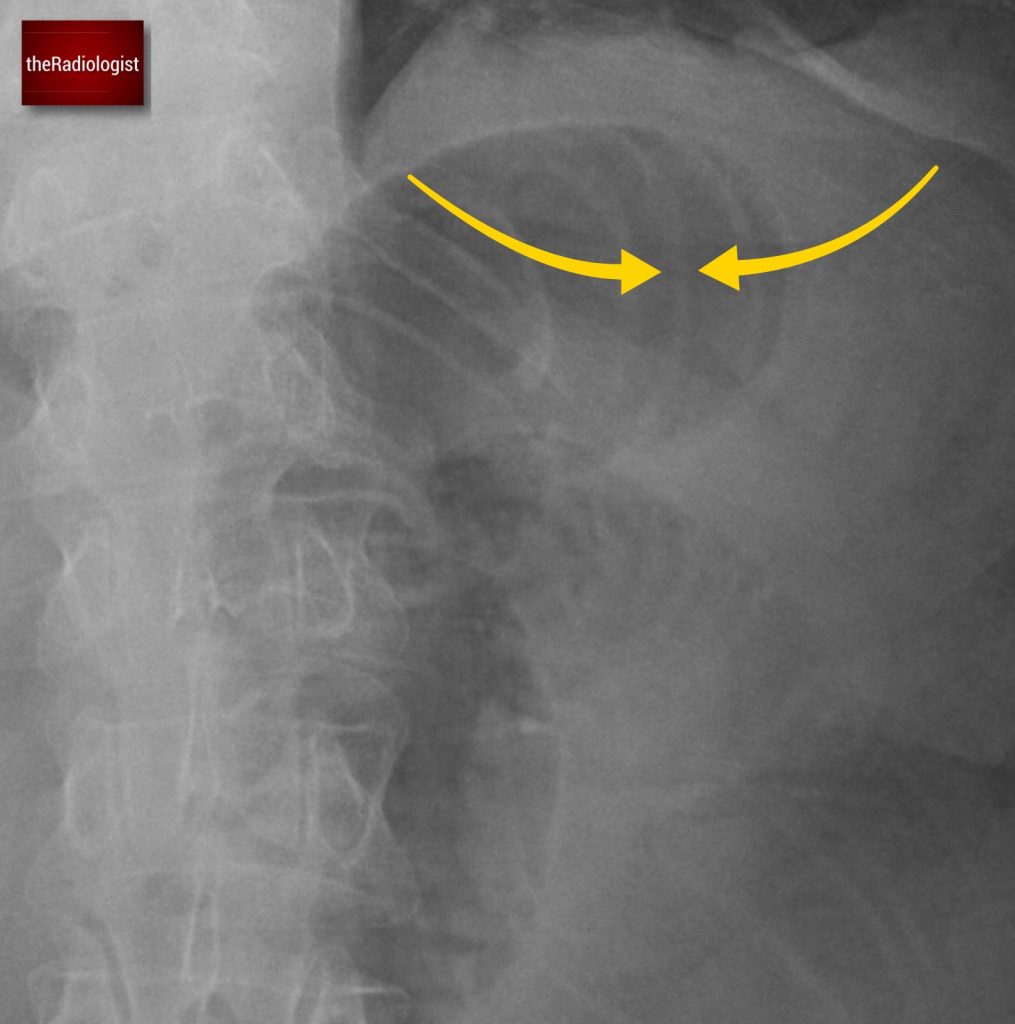

If we look at the psoas muscles on this scan below we can see there is some asymmetry . The right psoas is larger than the left and we’ve lost some of the fat planes within the muscle.

Compare the psoas muscles side by side. The right sided psoas muscle appears expanded with a loss of its normal fat planes.

Also as we scroll down we can see there is fat stranding surrounding the psoas muscle extending into the pelvis.

There is fat stranding surrounding the psoas extending into the pelvis.